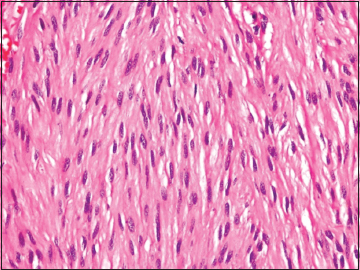

Investigation showed anemia with leukocytosis. Renal function tests and liver function tests were altered. Computed tomography of the abdomen showed dilated small bowel loops with free fluid. Preoperative diagnosis made as small intestine obstruction and planned for laparotomy. Intraoperative findings were small bowel obstruction due to jejuno-jejunal intussusception with jejunal gangrene [Figure 1] and [Figure 2]. Primary resection and anastomosis were performed due to the gangrenous bowel. Cut opened specimen of the jejunum showed an intraluminal mass lesion acting as a leading point for intussusception [Figure 3]. Postoperative histopathological examination showed proliferation of bland spindle cells with pale-to-eosinophilic fibrillar cytoplasm [Figure 4]. Tumor showed strong positive reaction for CD117 and CD34 with negative resected margin [Figure 5] and [Figure 6]. The above-mentioned findings confirmed the diagnosis of gastrointestinal stromal tumor (GIST). Postoperative recovery was uneventful.

| Figure. 4 Postoperative histopathology examination showing proliferation of bland spindle cells with pale-to-eosinophilic fibrillar cytoplasm with features of gastrointestinal stromal tumor